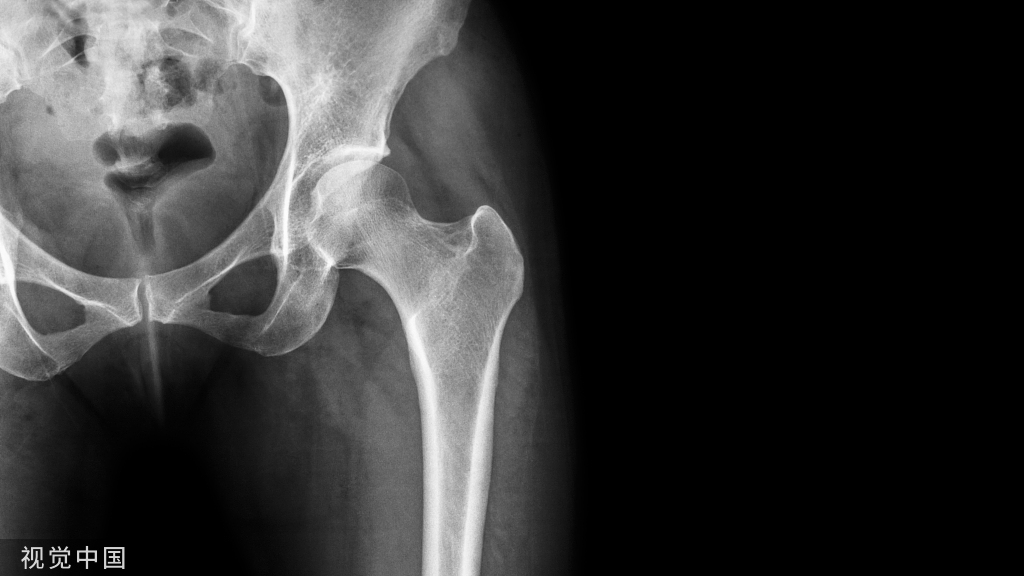

4部分骨折